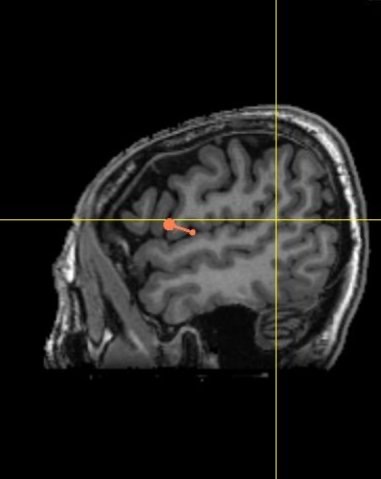

應用3D技術定位右側前額下迴(圖中橘色的指示記號)(長庚醫院提供)

由於背外側前額葉腦區跟執行功能、情緒調節以及固執行為相關;後顳上溝及右側前額下迴跟心智理論(將心比心的能力)相關,因此上述三個腦區被認為在自閉症的生物性治療中具有發展的潛力。

其中,我們使用Theta叢集性經顱磁刺激術對於右側前額下迴的刺激,在自閉症治療方面,有重大的突破。

長庚醫院這項研究為世界率先針對Theta叢集性經顱磁刺激術,刺激右側前額下迴在自閉症的隨機雙盲臨床試驗。研究共招募60位8-30歲的自閉者,將他們隨機且平均分配到治療組與對照刺激組,研究結果發現,在不需要麻醉的狀況下,每週2次,每次5分鐘內,連續8週刺激腦右側前額下迴,治療組比對照組顯著提升自閉症的社交認知功能,且治療效果可維持4週。